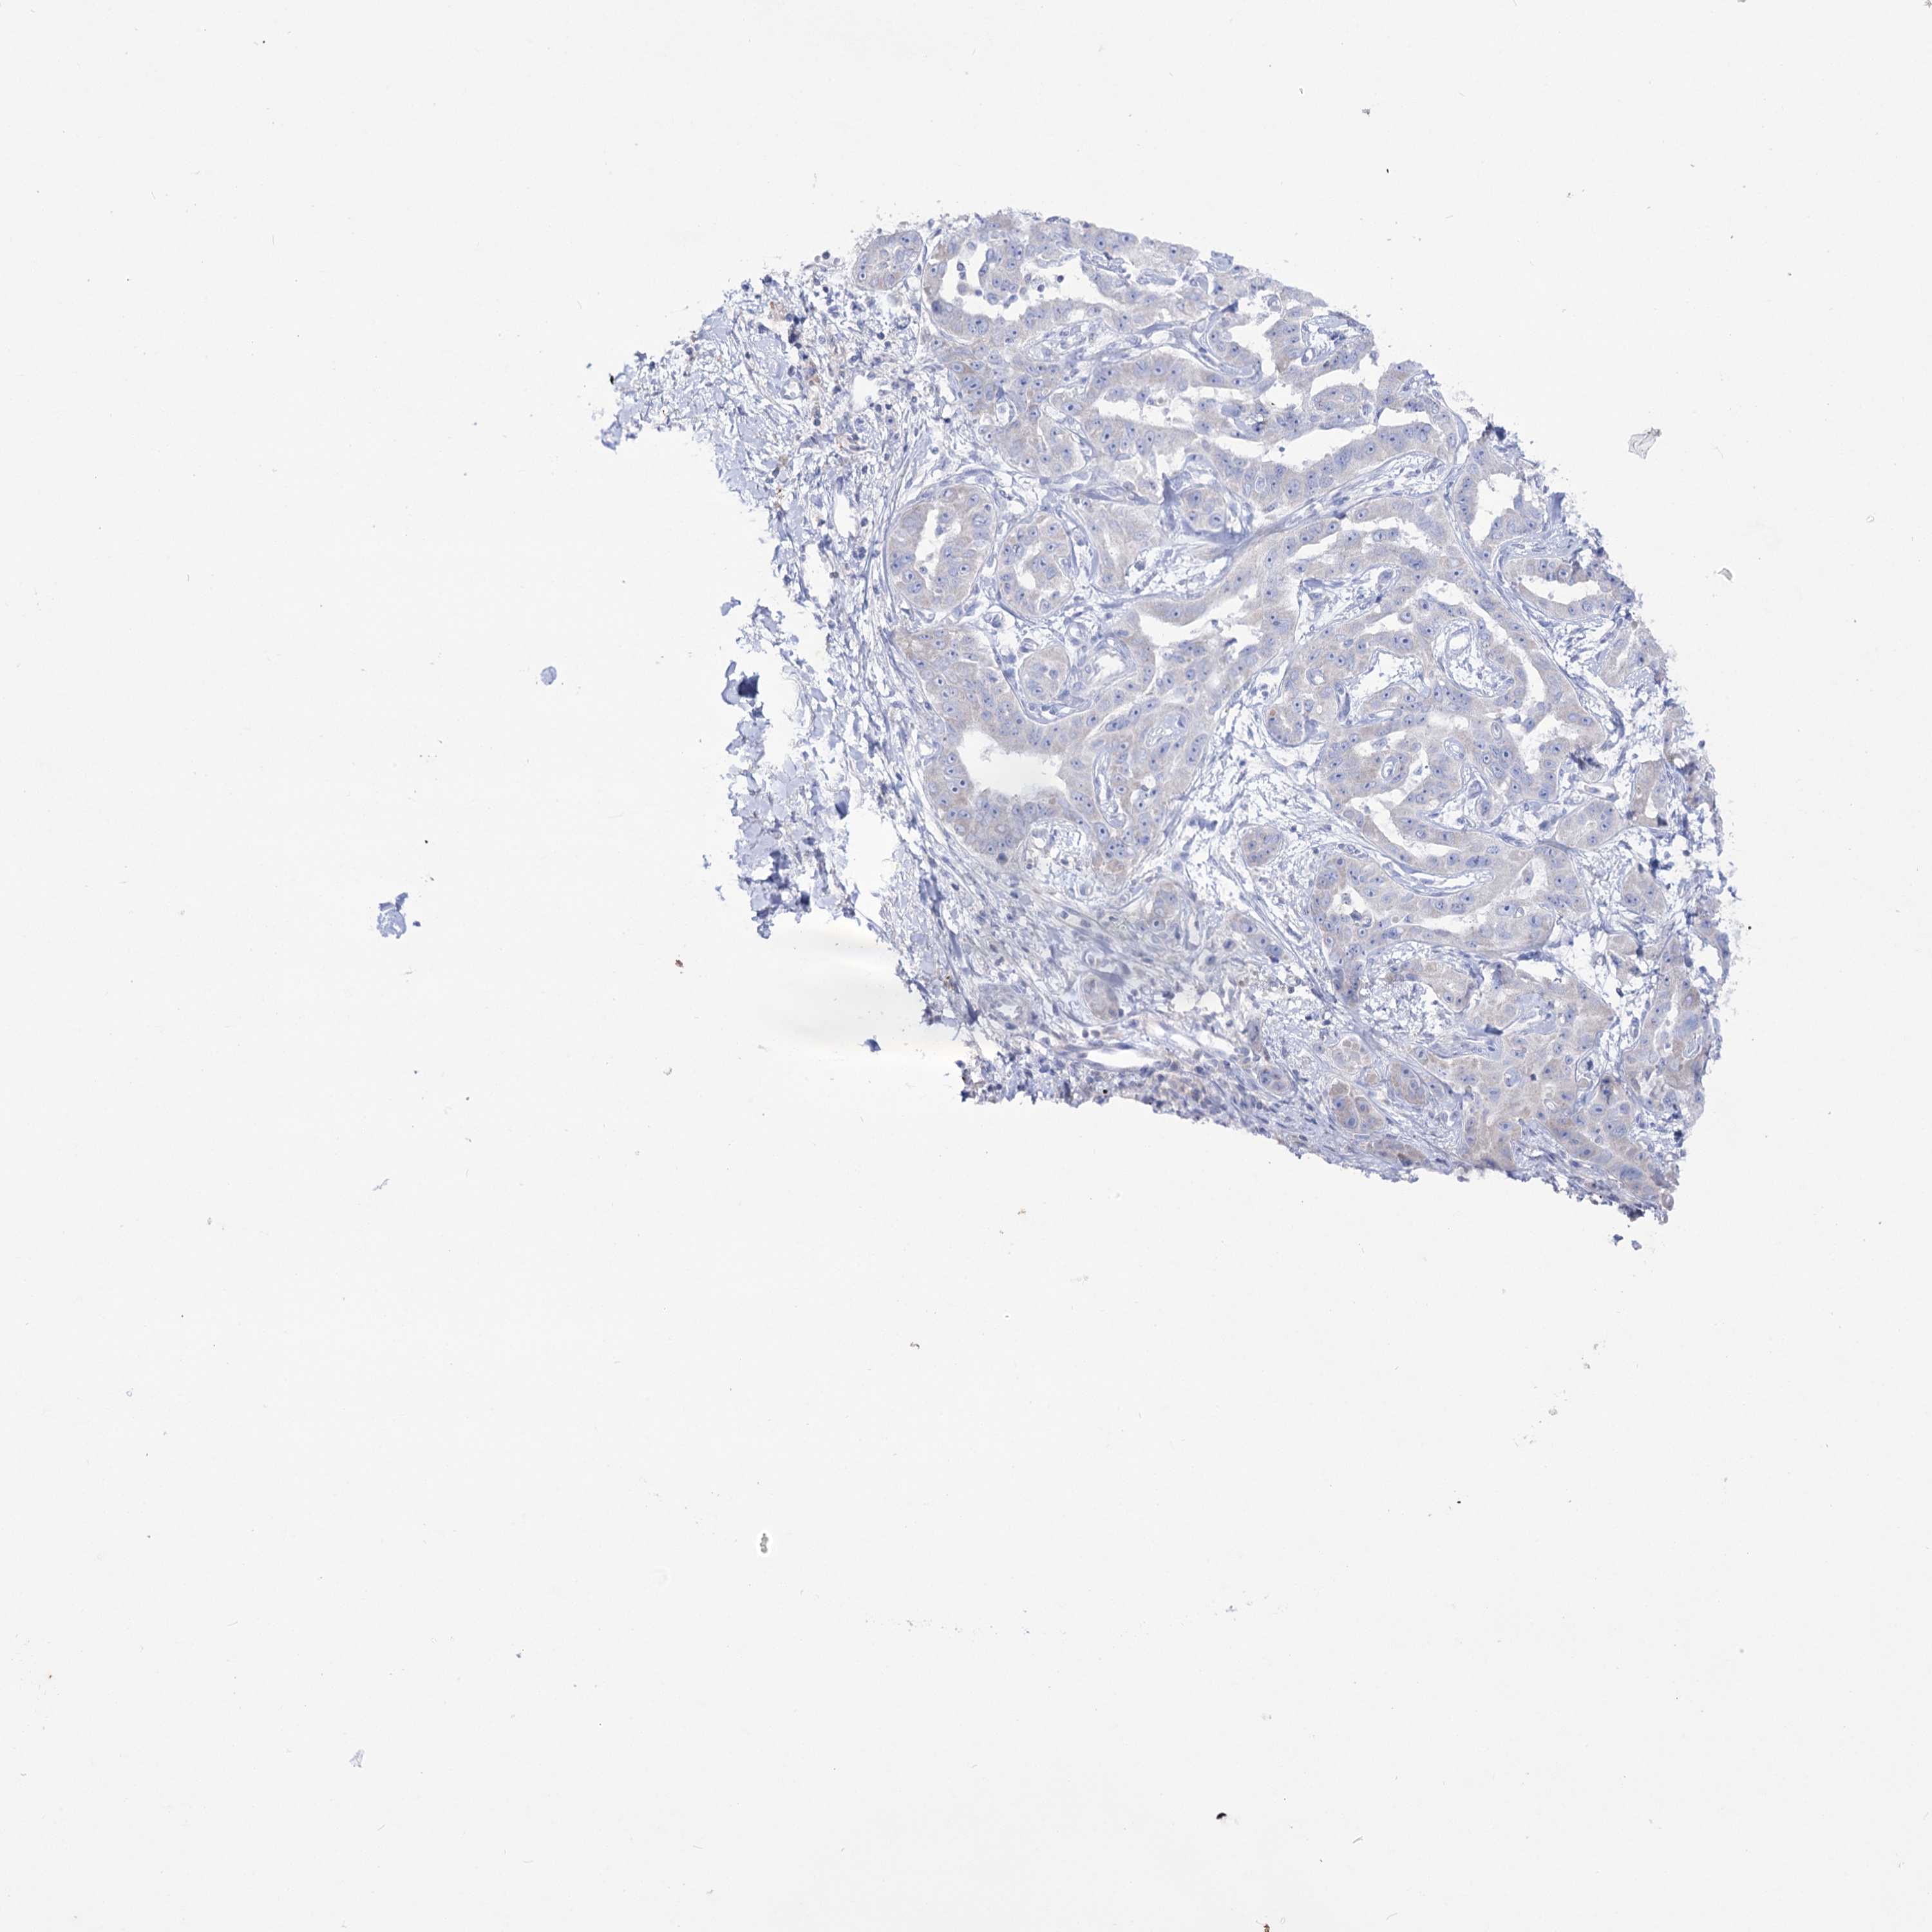

LIVER CANCER - Protein expressioni

A mouse-over function shows sample information and annotation data. Click on an image to view it in a full screen mode. Samples can be filtered based on level of antibody staining by selecting one or several of the following categories: high, medium, low and not detected. The assay and annotation is described here.

Note that samples used for immunohistochemistry by the Human Protein Atlas do not correspond to samples in the TCGA dataset.

Antibody stainingi

Antibody staining in the annotated cell types in the current human tissue is reported as not detected, low, medium, or high, based on conventional immunohistochemistry profiling in selected tissues. This score is based on the combination of the staining intensity and fraction of stained cells.

Each image is clickable and will lead to virtual microscopy that enables deeper exploration of all samples and also displays staining intensity scores, fraction scores and subcellular localization as well as patient and tissue information for each sample.

Antibody HPA038815

Staining

High

Medium

Low

Not detected

Intensity

Strong

Moderate

Weak

Negative

Quantity

>75%

75%-25%

<25%

None

Location

Nuclear

Cytoplasmic/membranous

Cytoplasmic/membranous,nuclear

Cholangiocarcinoma

Carcinoma, Hepatocellular, NOS